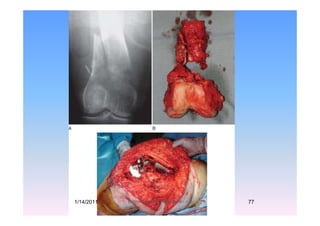

Supracondylar Femoral metsSupracondylar Femoral mets

Metastatic lesions of the distal femoral diaphysis &Metastatic lesions of the distal femoral diaphysis &

condyles are best treated by medial and lateral

Zickel rods with PMMAZickel rods with PMMA.

Large distal femoral metaph seal lesionsLarge distal femoral metaphyseal lesions,

especially those associated with intra-p y

articular extension and/or large soft-tissue

components Custom or modular distalcomponents, Custom or modular distal

femoral endoprosthetic replacement.

1/14/2011 77Professor Freih AbuHassan -UJ

MetastaticMetastatic

lung Ca.